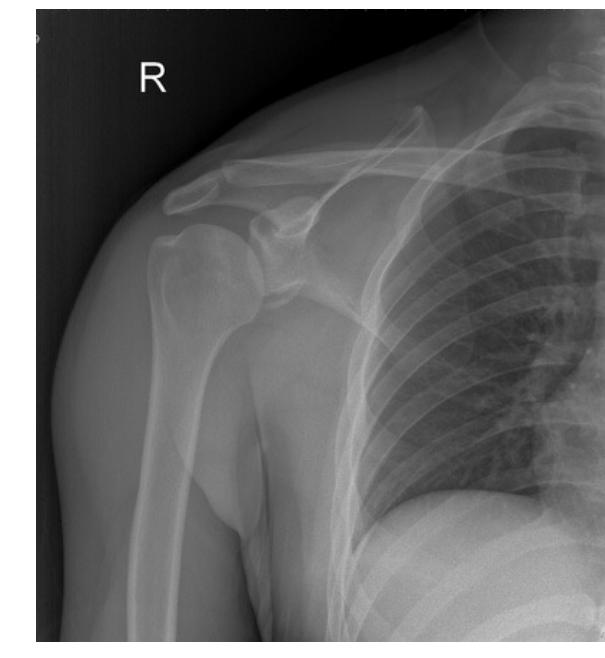

What is the diagnosis shown in the image?

- Anterior Shoulder Dislocation

- Axillary nerve injury

18-year-old male presented after sport injury and unable to do internal rotation of right shoulder. What is the name of the injury seen in the figure?

- Hill-Sachโs defect

- Hill-Sachs lesion

- Hill sachs lesion